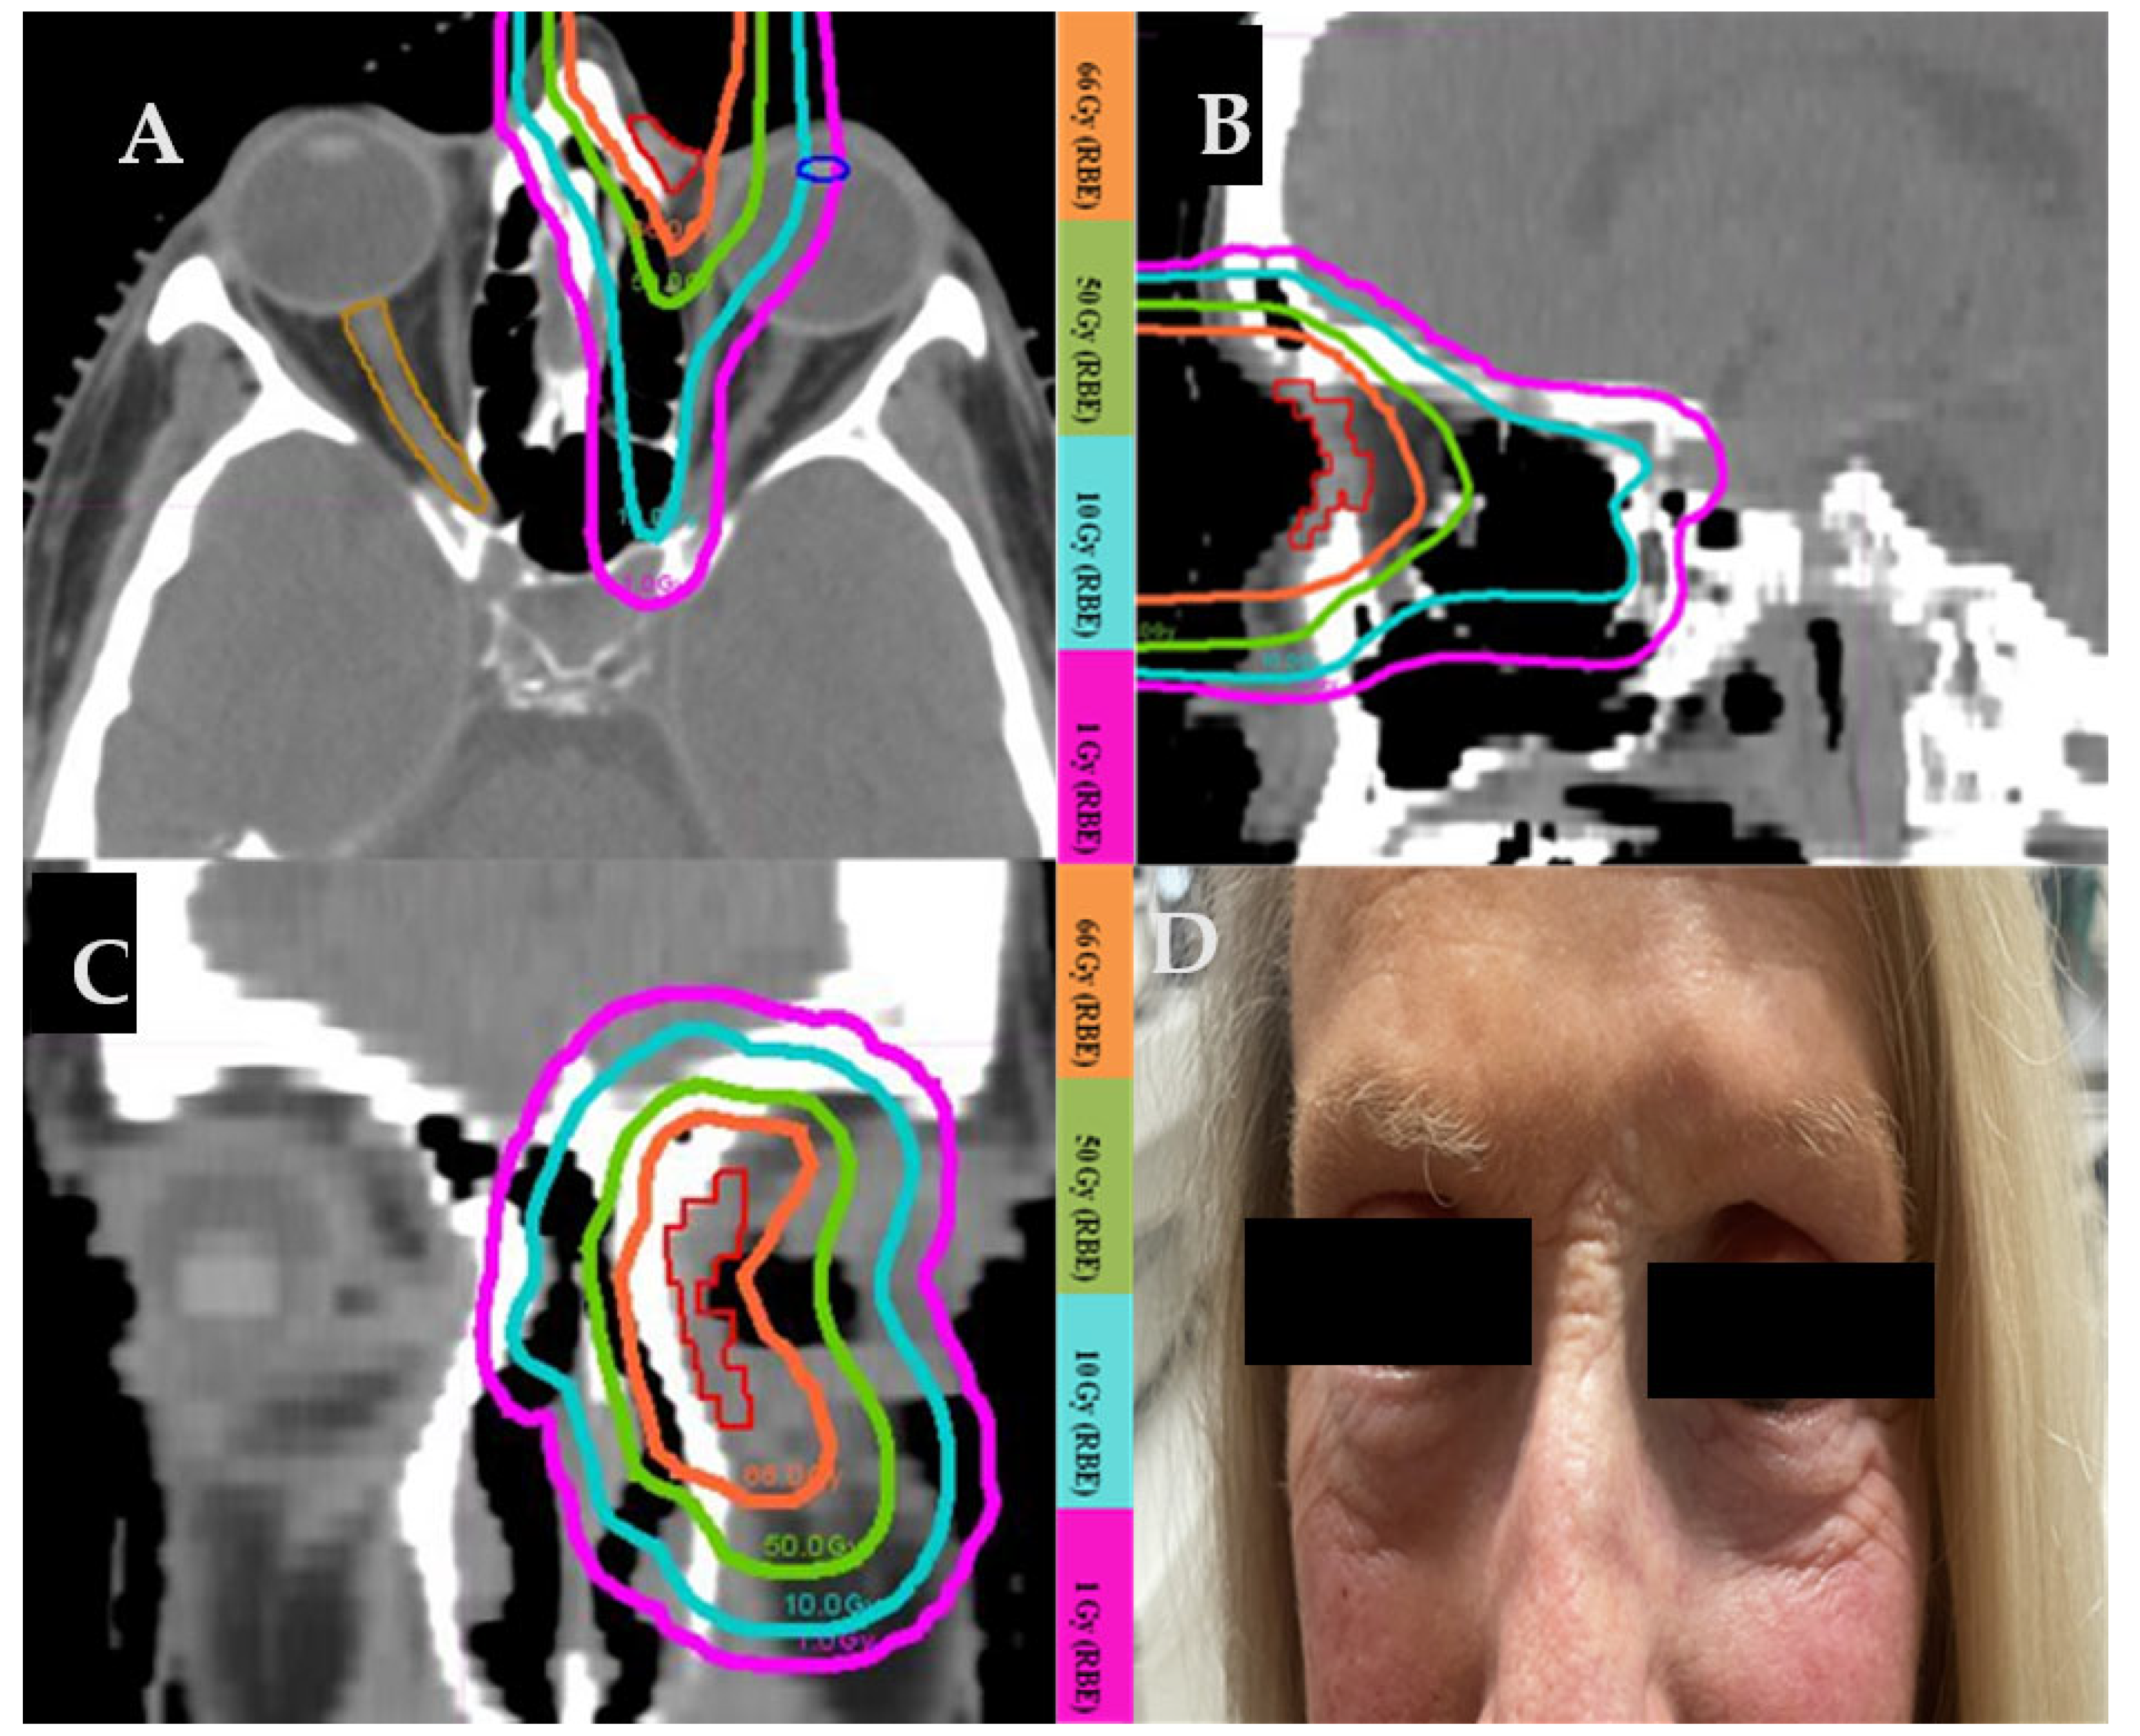

3.4.1. Case 1 (Figure 1)

An 80-year-old female with squamous cell carcinoma on the left lateral canthus with the involvement of the lateral orbital rim, lacrimal gland, and lateral rectus muscle. A light thin pink line delineates the gross tumor at the time of proton beam therapy (Figure 1A). The patient had undergone a partial resection. Gross total resection would involve orbital exenteration of the normal-functioning eye. The patient underwent proton beam therapy to a total dose of 66 Gy(RBE) (Figure 1A,B). During a 12-year follow-up after protons, the tumor was under control with excellent visual and cosmetic outcomes. With the use of protons, the left lens and the left optic nerve received 1 Gy(RBE) or less, despite being only millimeters away from the tumor target. Figure 1C,D, and Figure 1E,F showed the six MV IMRT and six MeV electron plans of the same patient, respectively. Figure 1G shows the photograph taken 60 months after the completion of proton therapy. The patient was able to preserve her vision and did not develop any long-term side effects from protons other than a very mild skin telangiectasia in the irradiated area and loss of the lateral aspect of the left eyebrow. Figure 1H shows the comparison of doses to the organs at risk with protons, IMRT, and electron plans. Protons are less penetrating and exhibit less lateral scattering than electrons and IMRT. Protons result in significantly lower maximal and mean doses to all organs at risk when compared to electrons or IMRT.

Figure 1. (A) Proton treatment plan. (B) Dose-volume histogram (DVH) of the proton plan in Figure 1A. (C) IMRT treatment plan. (D) DVH of the IMRT plan in Figure 1C. (E) Electron treatment plan. (F) DVH of the electron treatment plan in Figure 1E. (G) Picture of the treated area in the left lateral canthus taken 5 years after the completion of proton beam therapy. (H) Comparison of doses to the organs at risk with protons, IMRT, and electrons.